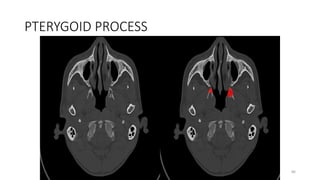

PTERYGOID PROCESS